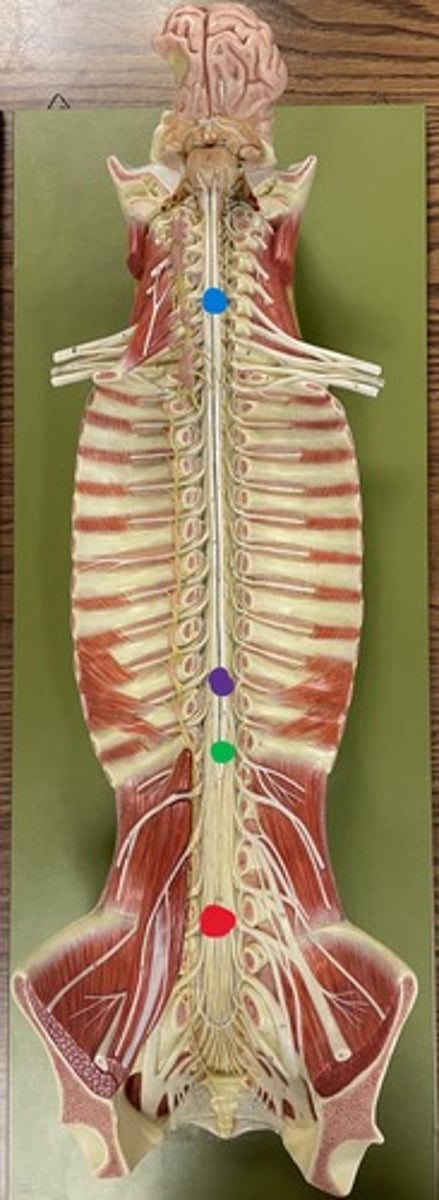

Cervical enlargement

Blue

Lumbar enlargement

Purple

Conus medullaris

Green

Cauda equina

Red